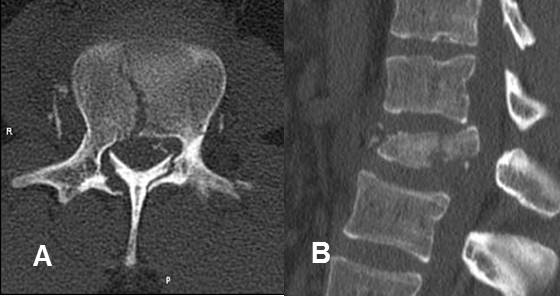

Fig 186. Fractura por explosión.

A: TAC axial y B: TAC reconstrucción sagital. Fractura conminuta del cuerpo vertebral, con compromiso de la columna anterior, media y posterior y fragmento retropulsado.